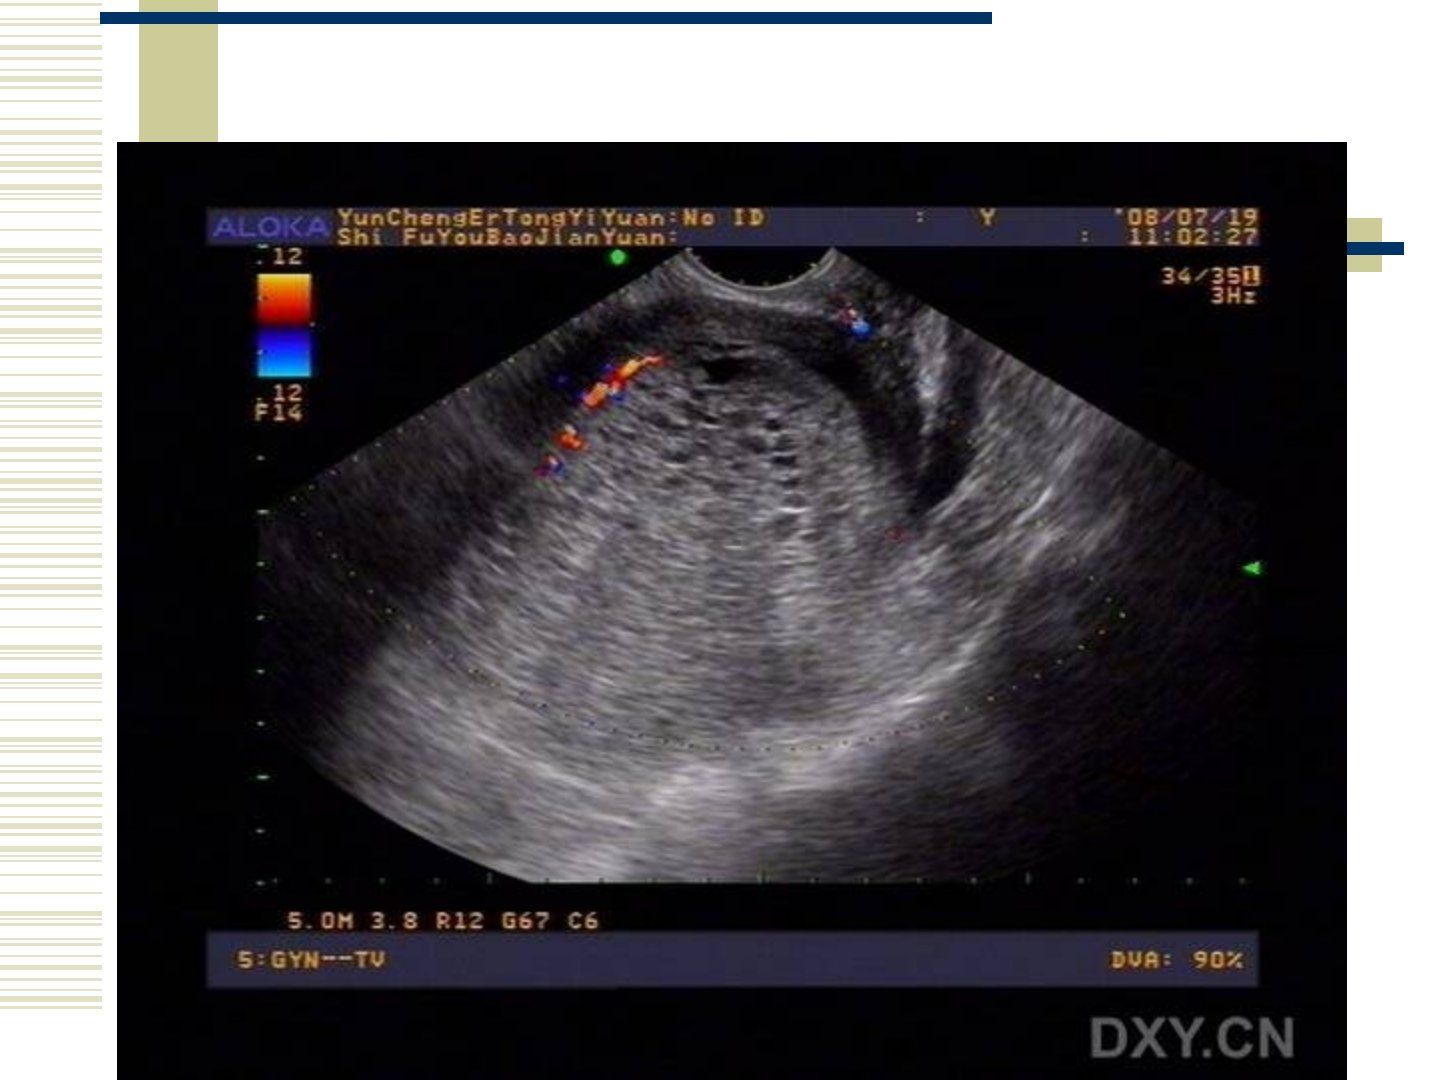

妊娠滋养细胞疾病包括葡萄胎、侵蚀性葡萄胎、绒毛膜癌及胎盘部位滋养细胞肿瘤。葡萄胎在停经45周时阴道B超可见妊娠囊5周可见胚芽和原始心管搏动。其发生与地域、种族、前次妊娠史、营养因素及细胞遗传异常有关。病理上完全性葡萄胎表现为绒毛体积增大、间质水肿、绒毛内血管消失部分性葡萄胎则仅部分绒毛变为水泡且合并有胚胎或胎儿组织。临床表现包括停经后阴道流血、子宫异常增大、妊娠剧吐、子痫前期征象、甲状腺功能亢进征象、腹痛及卵巢黄素化囊肿等。诊断依据临床表现、血清HCG测定及B超检查。治疗首选清宫术高危患者可考虑预防性化疗。随访中HCG定量测定极为重要需持续监测1年并严格避孕。侵蚀性葡萄胎和绒毛膜癌多继发于葡萄胎具有恶性行为治疗以化疗为主辅以手术和放疗。胎盘部位滋养细胞肿瘤临床罕见预后好确诊靠组织学检查手术是首选治疗方法术后随访同侵蚀性葡萄胎及绒毛膜癌。